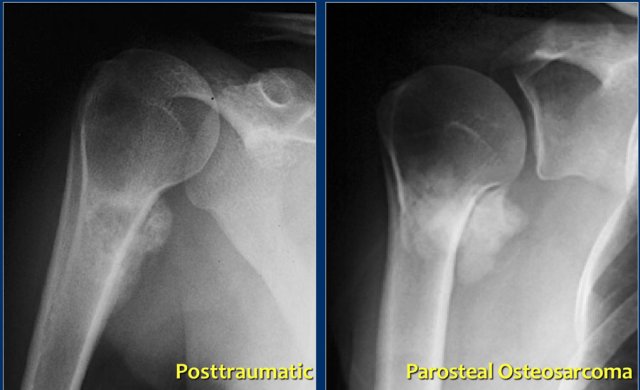

Posttraumatic calcifications

Here a patient with a juxtacortical sclerotic mass of the proximal humerus (left).

This proved to be a reactive calcification secondary to trauma.

Notice the resemblance to a juxtacortical mass in another patient (right), which was a biopsy proven parosteal osteosarcoma.

This shows that differentiating a tumor from a reactive proces scan be quite difficult in some cases.

When a reactive process is more likely based on history and imaging features, follow-up is sometimes still needed.